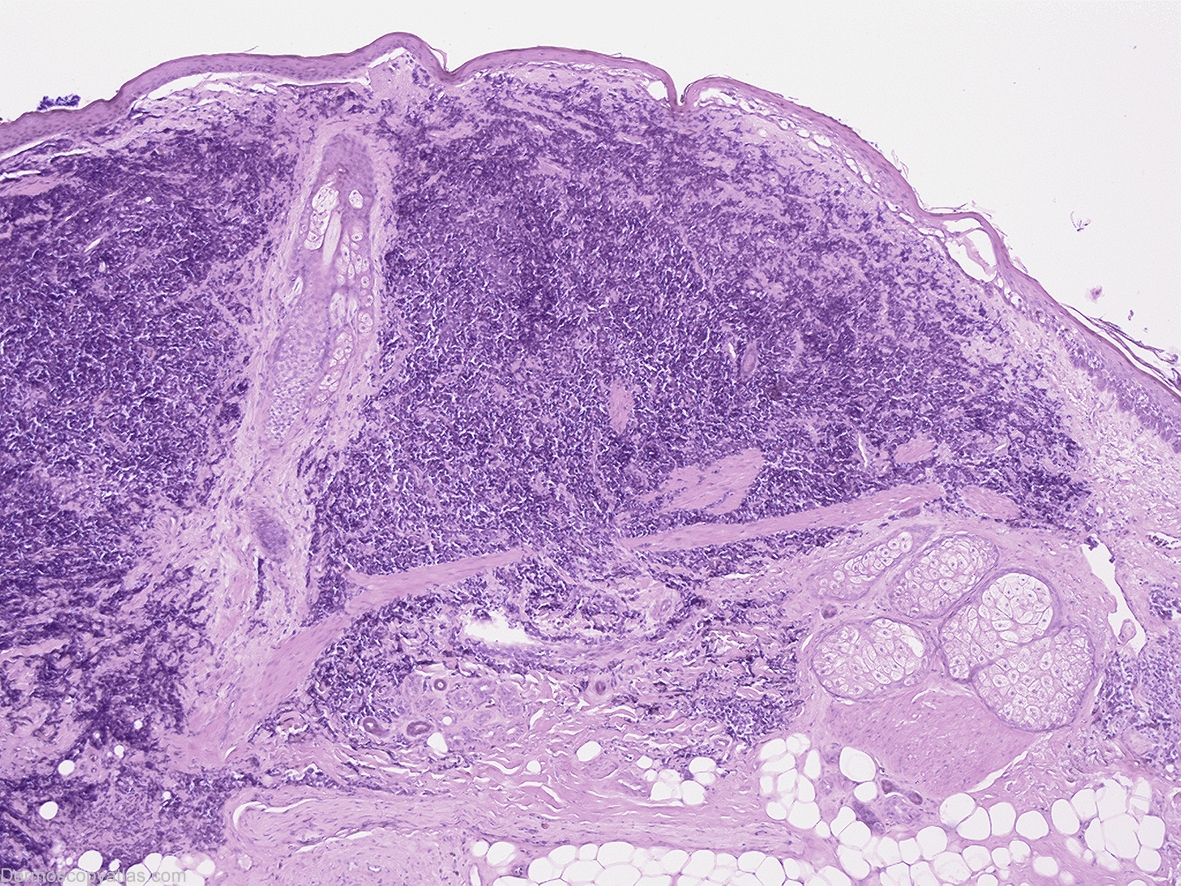

Image Number #2841 (Merkel cell carcinoma)

Site: Scalp

Diagnosis: Merkel cell carcinoma

History: This 83 year old gentleman presented for a routine skin check and this lesion was discovered. Prior to biopsy this lesion was lasered without biopsy by another practitioner but subsequent wide excision of the area discovered a residual dermal based Merkel cell carcinoma at the site where this lesion had been.